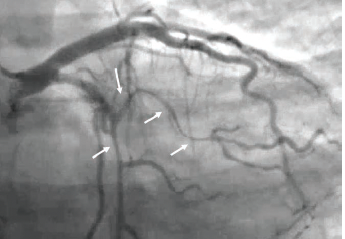

Patient 1 is a woman in her 50s, with chronic back pain, hypertension, and remote history of a transient ischemic attack (TIA). She presented to the emergency department with chest pain and elevated high sensitivity troponins >80,000 and was taken to the cath lab. She was found to have type II spontaneous coronary artery dissection in the mid to distal left anterior descending (LAD) coronary artery (Figures 1-2; Video 1). The right coronary artery (RCA) was normal. Of note, the patient had a similar presentation more than 1 year ago with high sensitivity troponins >16,000. The angiogram was normal (Figure 3; Video 2).

Jacqueline Saw, University of British Columbia, Vancouver, British Columbia: For patient 1, I urge you to relook at the high 1st diagonal artery on the 2022 angiogram. From the one angiogram projection that was provided, it looks like there is diffuse narrowing (type 2) SCAD of this high diagonal artery. Please look at other cranial projections to hunt for it. Also look for wall motion abnormality on the left ventriculogram. I assume there will be lateral hypokinesis corresponding to the high troponin >16,000. In fact, when you compared to the right anterior oblique (RAO) cranial angiogram of 2024, this high 1st diagonal is of larger caliber (healed).